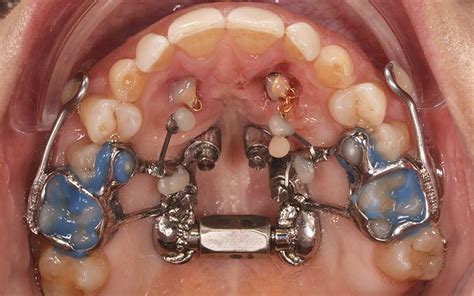

Fenestración y Tracción de Caninos

Cuando el problema que plantea el paciente es la inclusión de los caninos en la zona palatina, lo más recomendable es recurrir a la fenestración dental combinada con el posterior tratamiento ortodóncico. Aunque la fenestración de la pieza dental está condicionada por las particularidades de la boca de cada paciente, en el caso de los colmillos impactados resulta la solución más ventajosa. Gracias a la fenetración y tracción de caninos, se evitan las posibles consecuencias de un diente retenido.

La fenestración dental es un proceso indoloro y con un posoperatorio sencillo. Se trata de una cirugía ambulatoria realizada con anestesia local. Al finalizar la intervención se recomienda tomar algún tipo de calmante. Inmediatamente después de la cirugía de fenestración de caninos, se deben comer alimentos blandos y abundante líquido. Unos días después de la fenestración del colmillo se procede a la retirada de puntos.

Tras la retirada de hueso y mucosa en el área palatina, es normal sentir molestias. Durante los primeros días se ha de llevar una dieta blanda y extremar la higiene en el área afectada. Con la retirada de los puntos dará comienzo el proceso de tracción para desplazar el diente hasta su posición. El mejor consejo después de un procedimiento de este tipo es tener paciencia. Unos días después de la fenestración del colmillo se procede a la retirada de puntos.

Por norma general, una vez la pieza dental ha sido descubierta y se coloca el bracket, suele tardar entre 4 y 6 meses. No todos los caninos incluidos pueden ser reubicados. El cirujano oral y el ortodoncista trabajan de manera conjunta para determinar qué pacientes son aptos para este tipo de tratamientos.